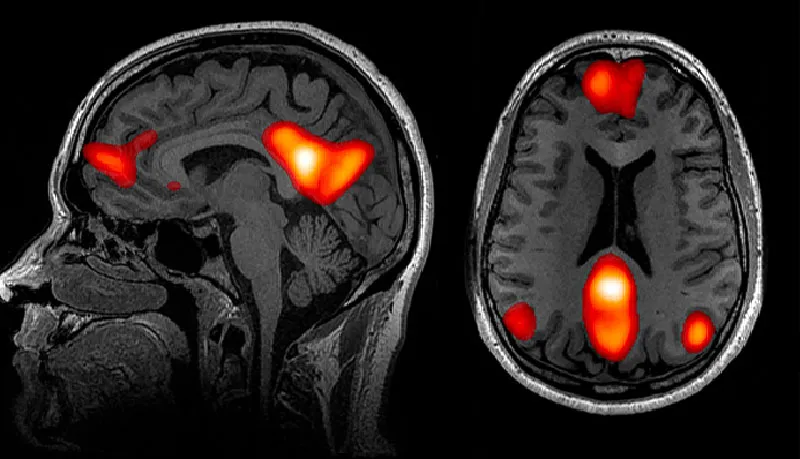

Результаты, опубликованные в 2020 году в журнале Nature Communications, показали, что очаг одиночества в мозге находится в сети пассивного режима работы мозга (СПРРМ) — той самой части мозга, которая активизируется, когда человек не занят решением каких-либо задач. «Всего 20 лет назад мы даже не знали, что у нас есть такая сеть», — сказал Бздок. Тем не менее исследования показали, что на активность СПРРМ приходится основная часть потребляемой мозгом энергии.

Как показали Бздок и его коллеги, некоторые области СПРРМ у хронически одиноких людей не только больше, но и сильнее связаны с другими областями мозга. Кроме того, СПРРМ, судя по всему, вовлечена во многие процессы, являющиеся особенностью человека разумного, — язык, прогнозирование будущего и причинно-следственное мышление. В общем, СПРРМ активируется тогда, когда мы думаем о других людях, в том числе когда мы истолковываем их намерения.

Функциональная магнитно-резонансная томография человеческого мозга выявляет области, связанные с СПРРМ — совокупностью нейронных центров, которые наиболее активны, когда мы думаем о других людях.

Результаты исследования связей СПРРМ позволили подтвердить открытия психологов нейровизуализационными данными. Согласно этим открытиям, одинокие люди склонны мечтать о социальном взаимодействии, ностальгировать о социальных событиях прошлого и даже очеловечивать своих питомцев, в частности разговаривать с ними как с людьми. «Для этого тоже требуется работа СППРМ», — комментирует Бздок.